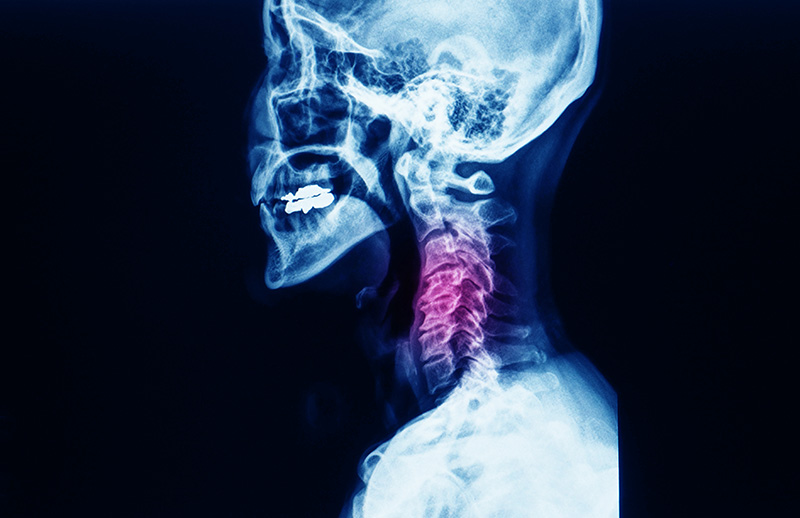

Beyin ve Sinir Cerrahisi, beyin ve omurilik bölgesindeki damar tıkanıklıkları, yaralanmalar ve bel ve boyun fıtığı gibi hastalıklara müdahale edildiği birime denilmektedir. Nöroşirürji adı da verilen Beyin ve Sinir Cerrahisi Birimi’nde çocukluktan yetişkinliğe kadar her yaş grubunda yaşanan sinir sistemi hastalıklarının tanı ve tedavileri gerçekleştirilmektedir.

Adana Özel Ortadoğu Hastanesi’nde Boyun ve Bel Fıtığı Ameliyatları, Beyin Ameliyatları, Periferik Sinir Ameliyatları, Ventrikülo Pertoneal Şantlama, Supratentorial Tümör Çıkartılması, Servikal Stenoz Ameliyatı, Çökme Kırığı Hasarı Ameliyatı, Anterior Servikal Diskektomi, Servikal Foraminatomi, Spinal Tümör Ameliyatı, Beynin Hasarlı Kısmının Çıkartılması, Periferik Sinir Sıkışması, Kafa İçi Hematom Boşaltılması ve Lomber Omurga ameliyatları başarı ile yapılmaktadır. Ameliyatlarla ilgile detaylı bilgilere aşağıdan ulaşabilirsiniz.